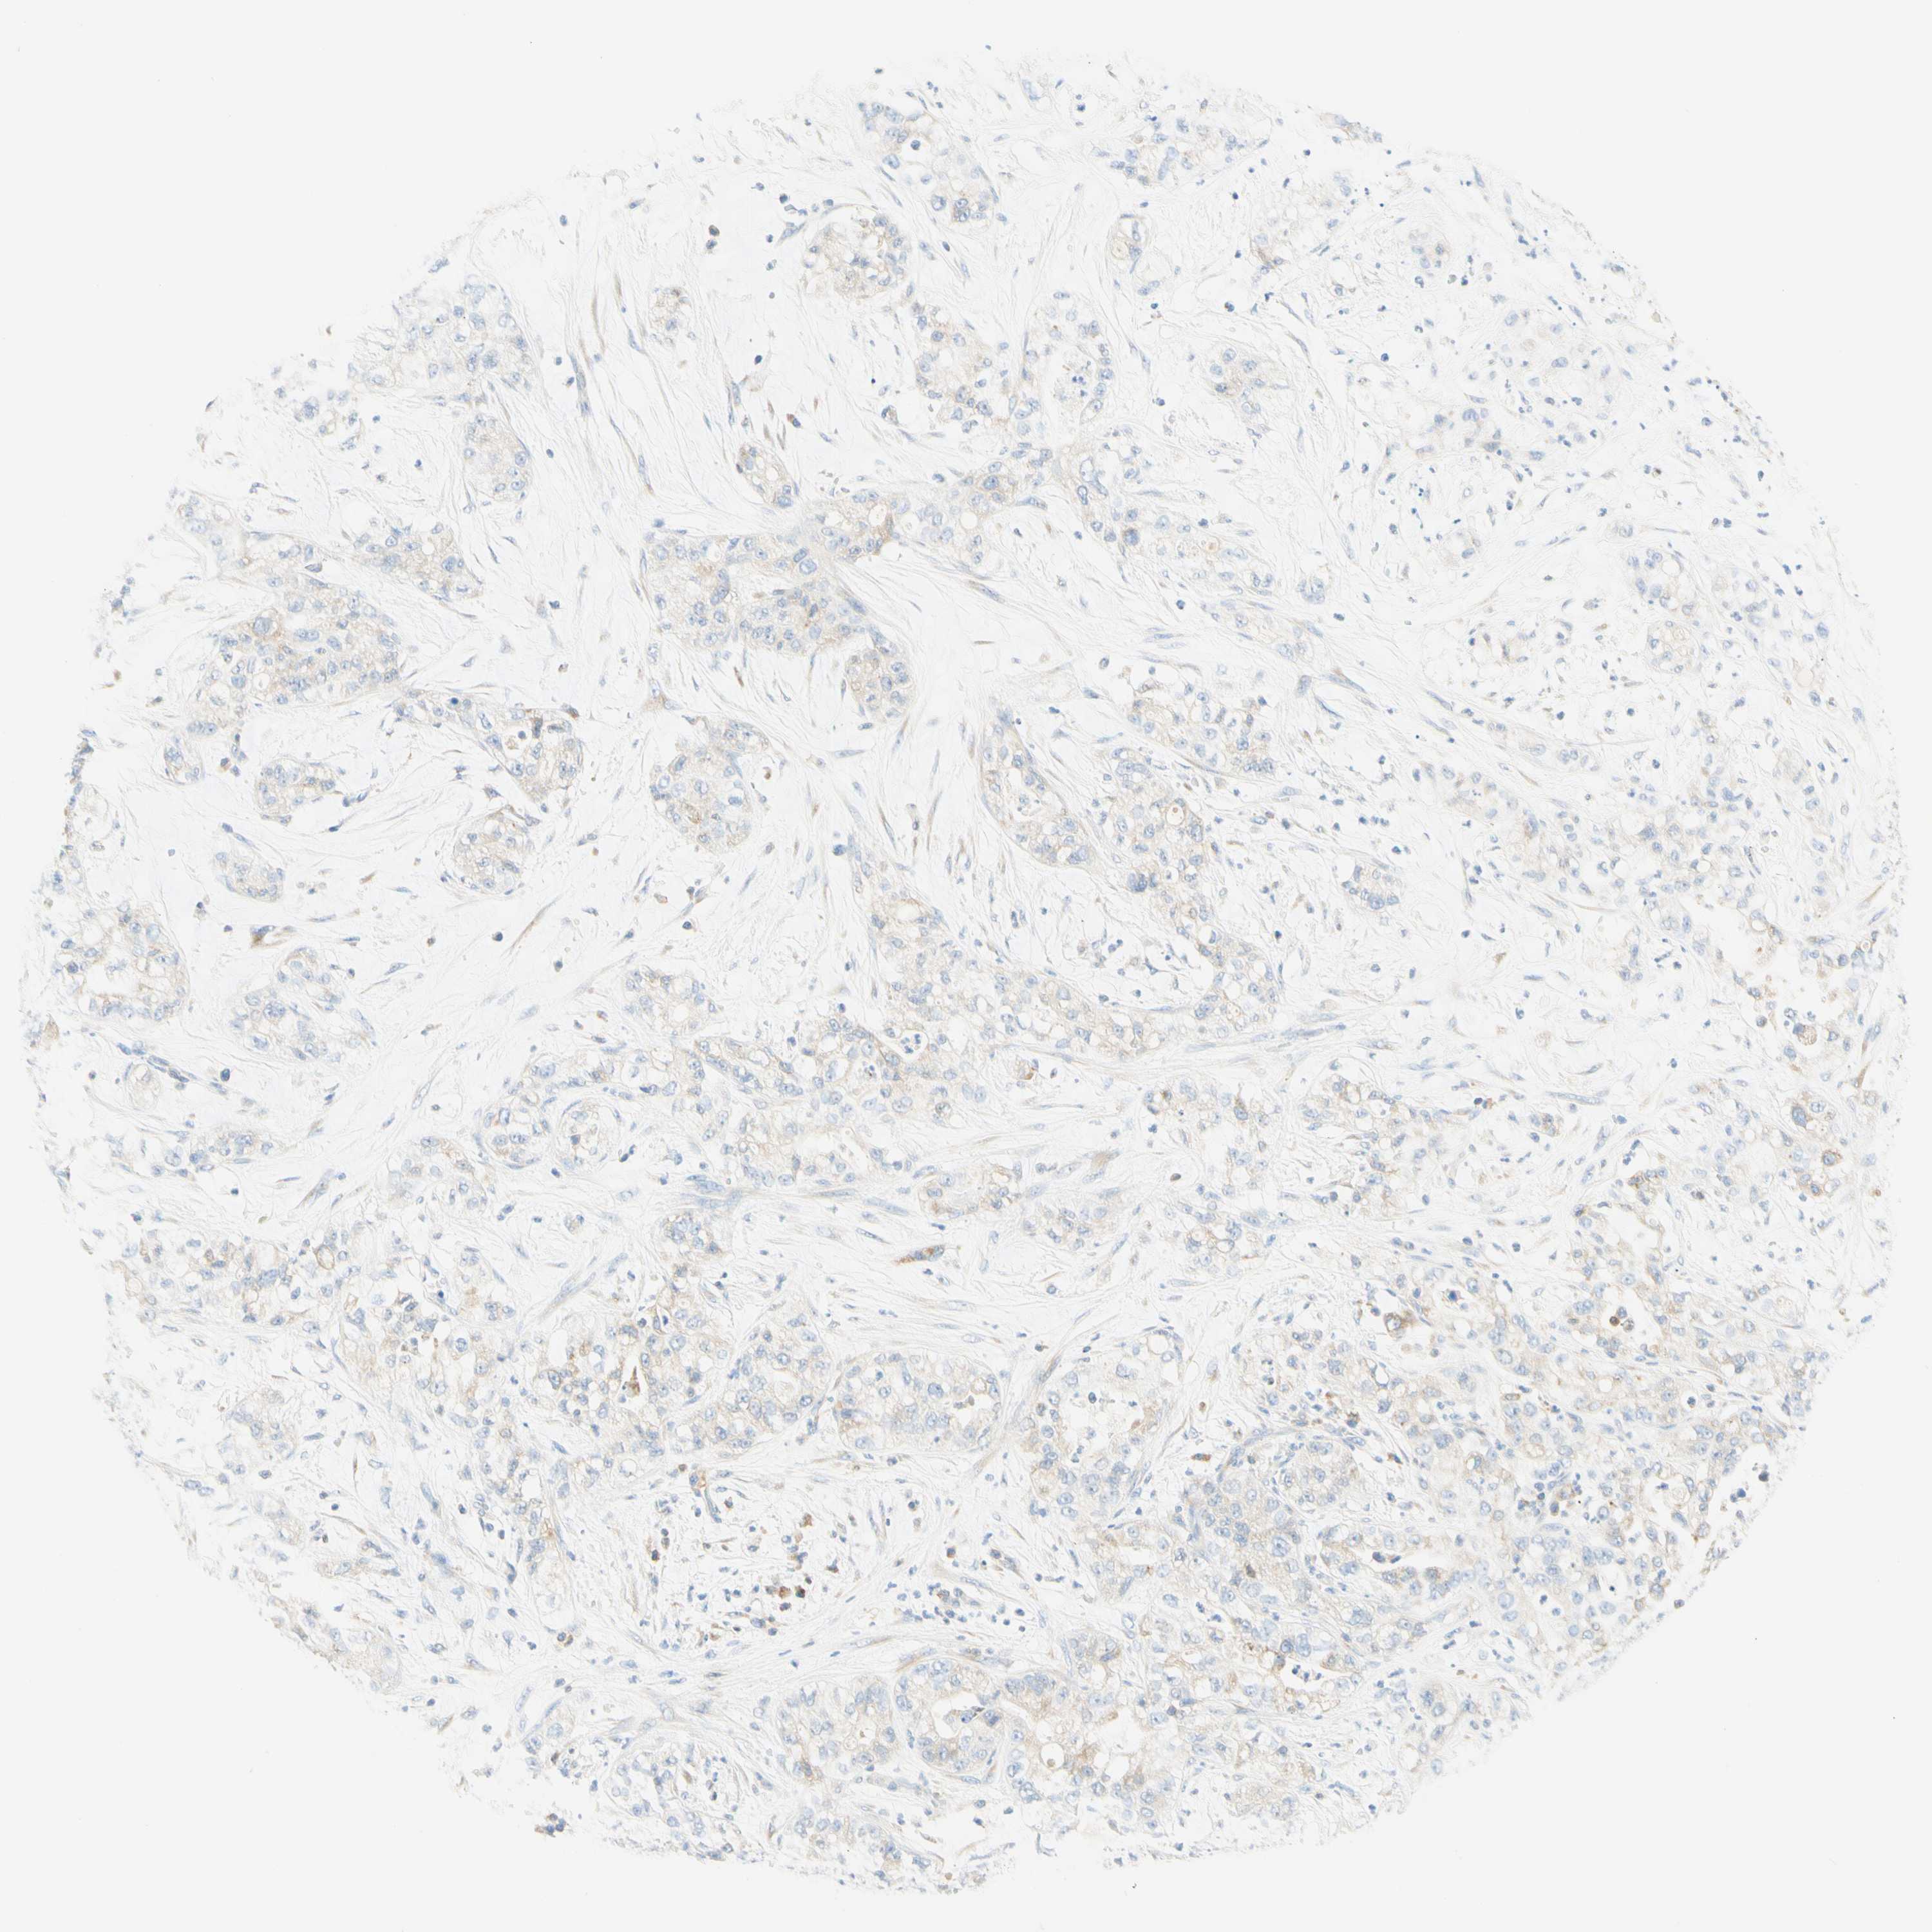

PANCREATIC CANCER - Protein expressioni

A mouse-over function shows sample information and annotation data. Click on an image to view it in a full screen mode. Samples can be filtered based on level of antibody staining by selecting one or several of the following categories: high, medium, low and not detected. The assay and annotation is described here.

Note that samples used for immunohistochemistry by the Human Protein Atlas do not correspond to samples in the TCGA dataset.

Antibody stainingi

Antibody staining in the annotated cell types in the current human tissue is reported as not detected, low, medium, or high, based on conventional immunohistochemistry profiling in selected tissues. This score is based on the combination of the staining intensity and fraction of stained cells.

Each image is clickable and will lead to virtual microscopy that enables deeper exploration of all samples and also displays staining intensity scores, fraction scores and subcellular localization as well as patient and tissue information for each sample.

Antibody HPA011157

Antibody CAB002223

Antibody CAB012978

Antibody CAB079960

Adenocarcinoma, NOS